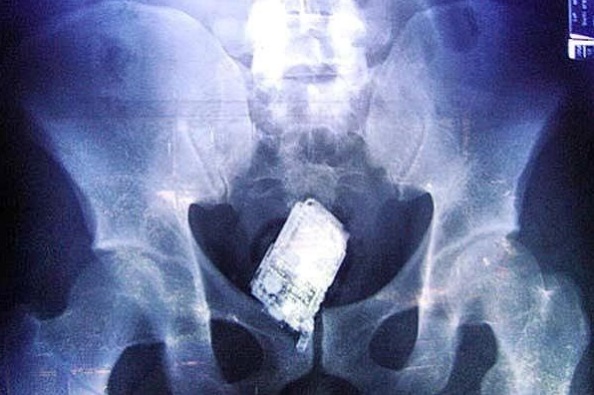

Homem dá entrada no Trauma de Campina com cerveja nas partes íntimas

Um atendimento neste fim de semana no Hospital de Emergência e Trauma de Campina Grande, chamou a atenção da equipe médica, pois um homem de 42 anos, morador da cidade de Queimadas, deu entrada no hospital e após ter um latão de cerveja inserido no ânus. Segundo informações da equipe médica, a vítima bebia na […]